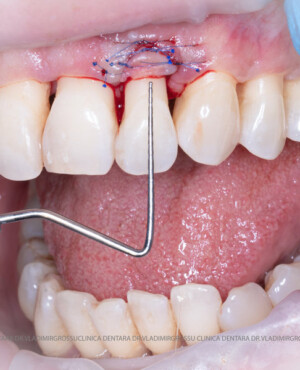

Adiția de gingie (gingivoplastia)

Aditia gingivală este o procedură chirurgicală ce corectează diverse probleme estetice și funcționale, cum ar fi recesiunea gingivală. În implantologia modernă, aditia de țesut moale este utilizată aproape în fiecare intervenție de inserție a implantului dentar pentru a asigura un aspect estetic natural și o bună integrare a implantului în cavitatea bucală.